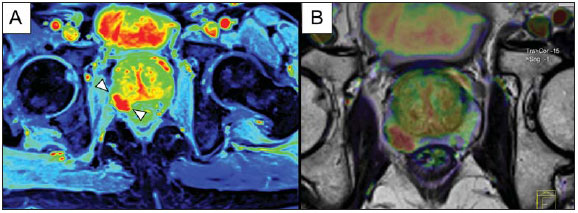

Neste exemplo, temos o pós-processamento semiquantitativo do DCE. A imagem A representa o mapa paramétrico gerado, correspondendo à área abaixo da curva durante o primeiro minuto (positive enhancement index – PEI). Observamos que neste mapa a área suspeita está codificada em vermelho (cabeças de seta), se destacando das outras porções do parênquima prostático. Em B é mostrada uma fusão entre o mapa paramétrico.